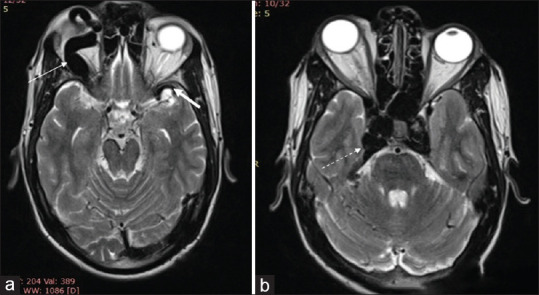

A 28-year-old Male with Complaints of Redness in the Right Eye with Proptosis: Direct Carotid-cavernous Fistula.

一位28岁男性,主诉右眼发红并突出:直接颈动脉海绵状瘘。